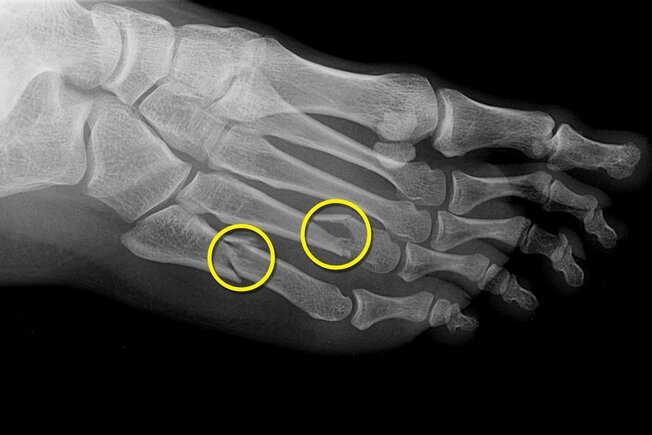

Fracturile de stres din cauza stresului

Sănătatea picioarelor este foarte importantă pentru menținerea mobilității la orice vârstă, așa că acest material va fi de interes pentru oricine îi pasă de picioarele lor.-16

16/17

La femei, modificările hormonale care vin odată cu menopauza pot reduce densitatea osoasă (osteoporoza) și pot crește riscul de fracturi osoase, inclusiv oasele de la picior. O fractură de stres necesită câteva săptămâni de odihnă pentru a se vindeca. Vă puteți întări oasele cu exerciții fizice, dietă și, eventual, medicamente și vitamine speciale. Întrebați-vă medicul despre riscuri, beneficii și ce va funcționa cel mai bine pentru dvs.